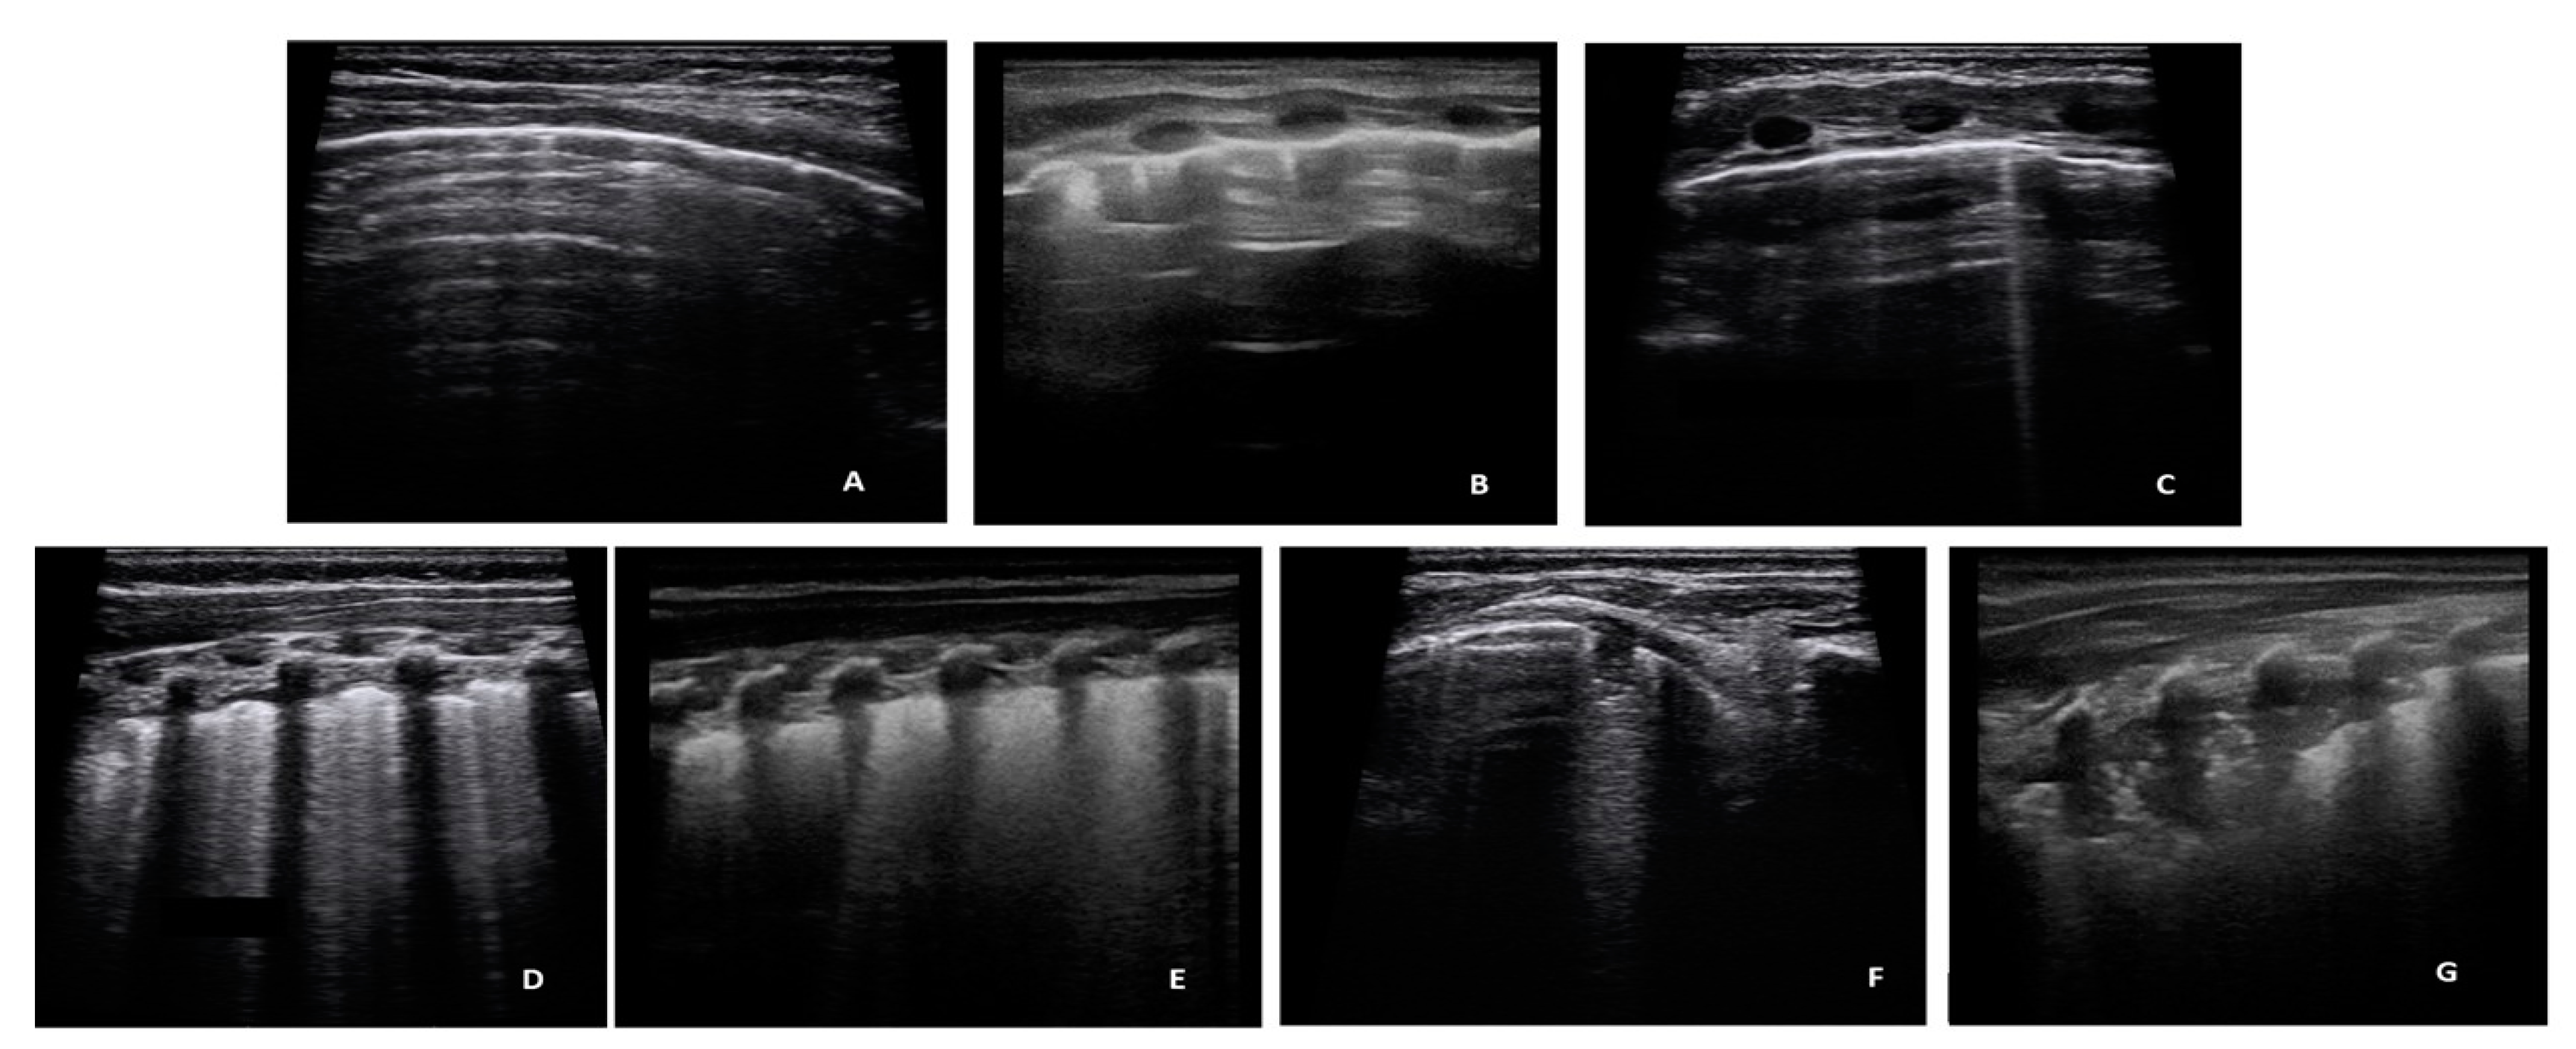

- A-lines: Horizontal reverbs of pleural line, normal ultrasound finding (Score 0 for the quantitative analysis, negative for the dycotomous analyses).

- Short vertical artifacts (SVA, artifacts that do not reach the bottom of the screen, using a depth setting of 3 cm) According to a recent hypothesis [34], short artifacts may be produced by small channel or by acoustic traps which allows a quick release of the trapped acoustic energy [33]. Acoustic traps of this type are compatible with simple geometries such as those caused by minimal superficial alveolar collapses. Their microatelectatic nature and easy reversibility, in our opinion, justifies their distinction from the usual artifacts (B-Lines).

- B-Lines showing a density of no more than 2 B lines per cm of the pleural line, with a depth setting of 3 cm, were described as Isolated B-Lines. Short vertical artifacts and Isolated B-Lines were considered clinically non-significant findings. Consequently, they were interpreted negative for dycotomous analyses, but received a score 1 for the quantitative analysis.

- Multiple B lines (Lines B with a distance between them of less than half a cm to the confluence, remaining identifiable from each other) were considered pathological findings (positive), with a quantitative score of 2.

- White lung (Subpleural field with various shades of white/gray without distinguishing lines B), pathological findings (positive), with a quantitative score of 3.